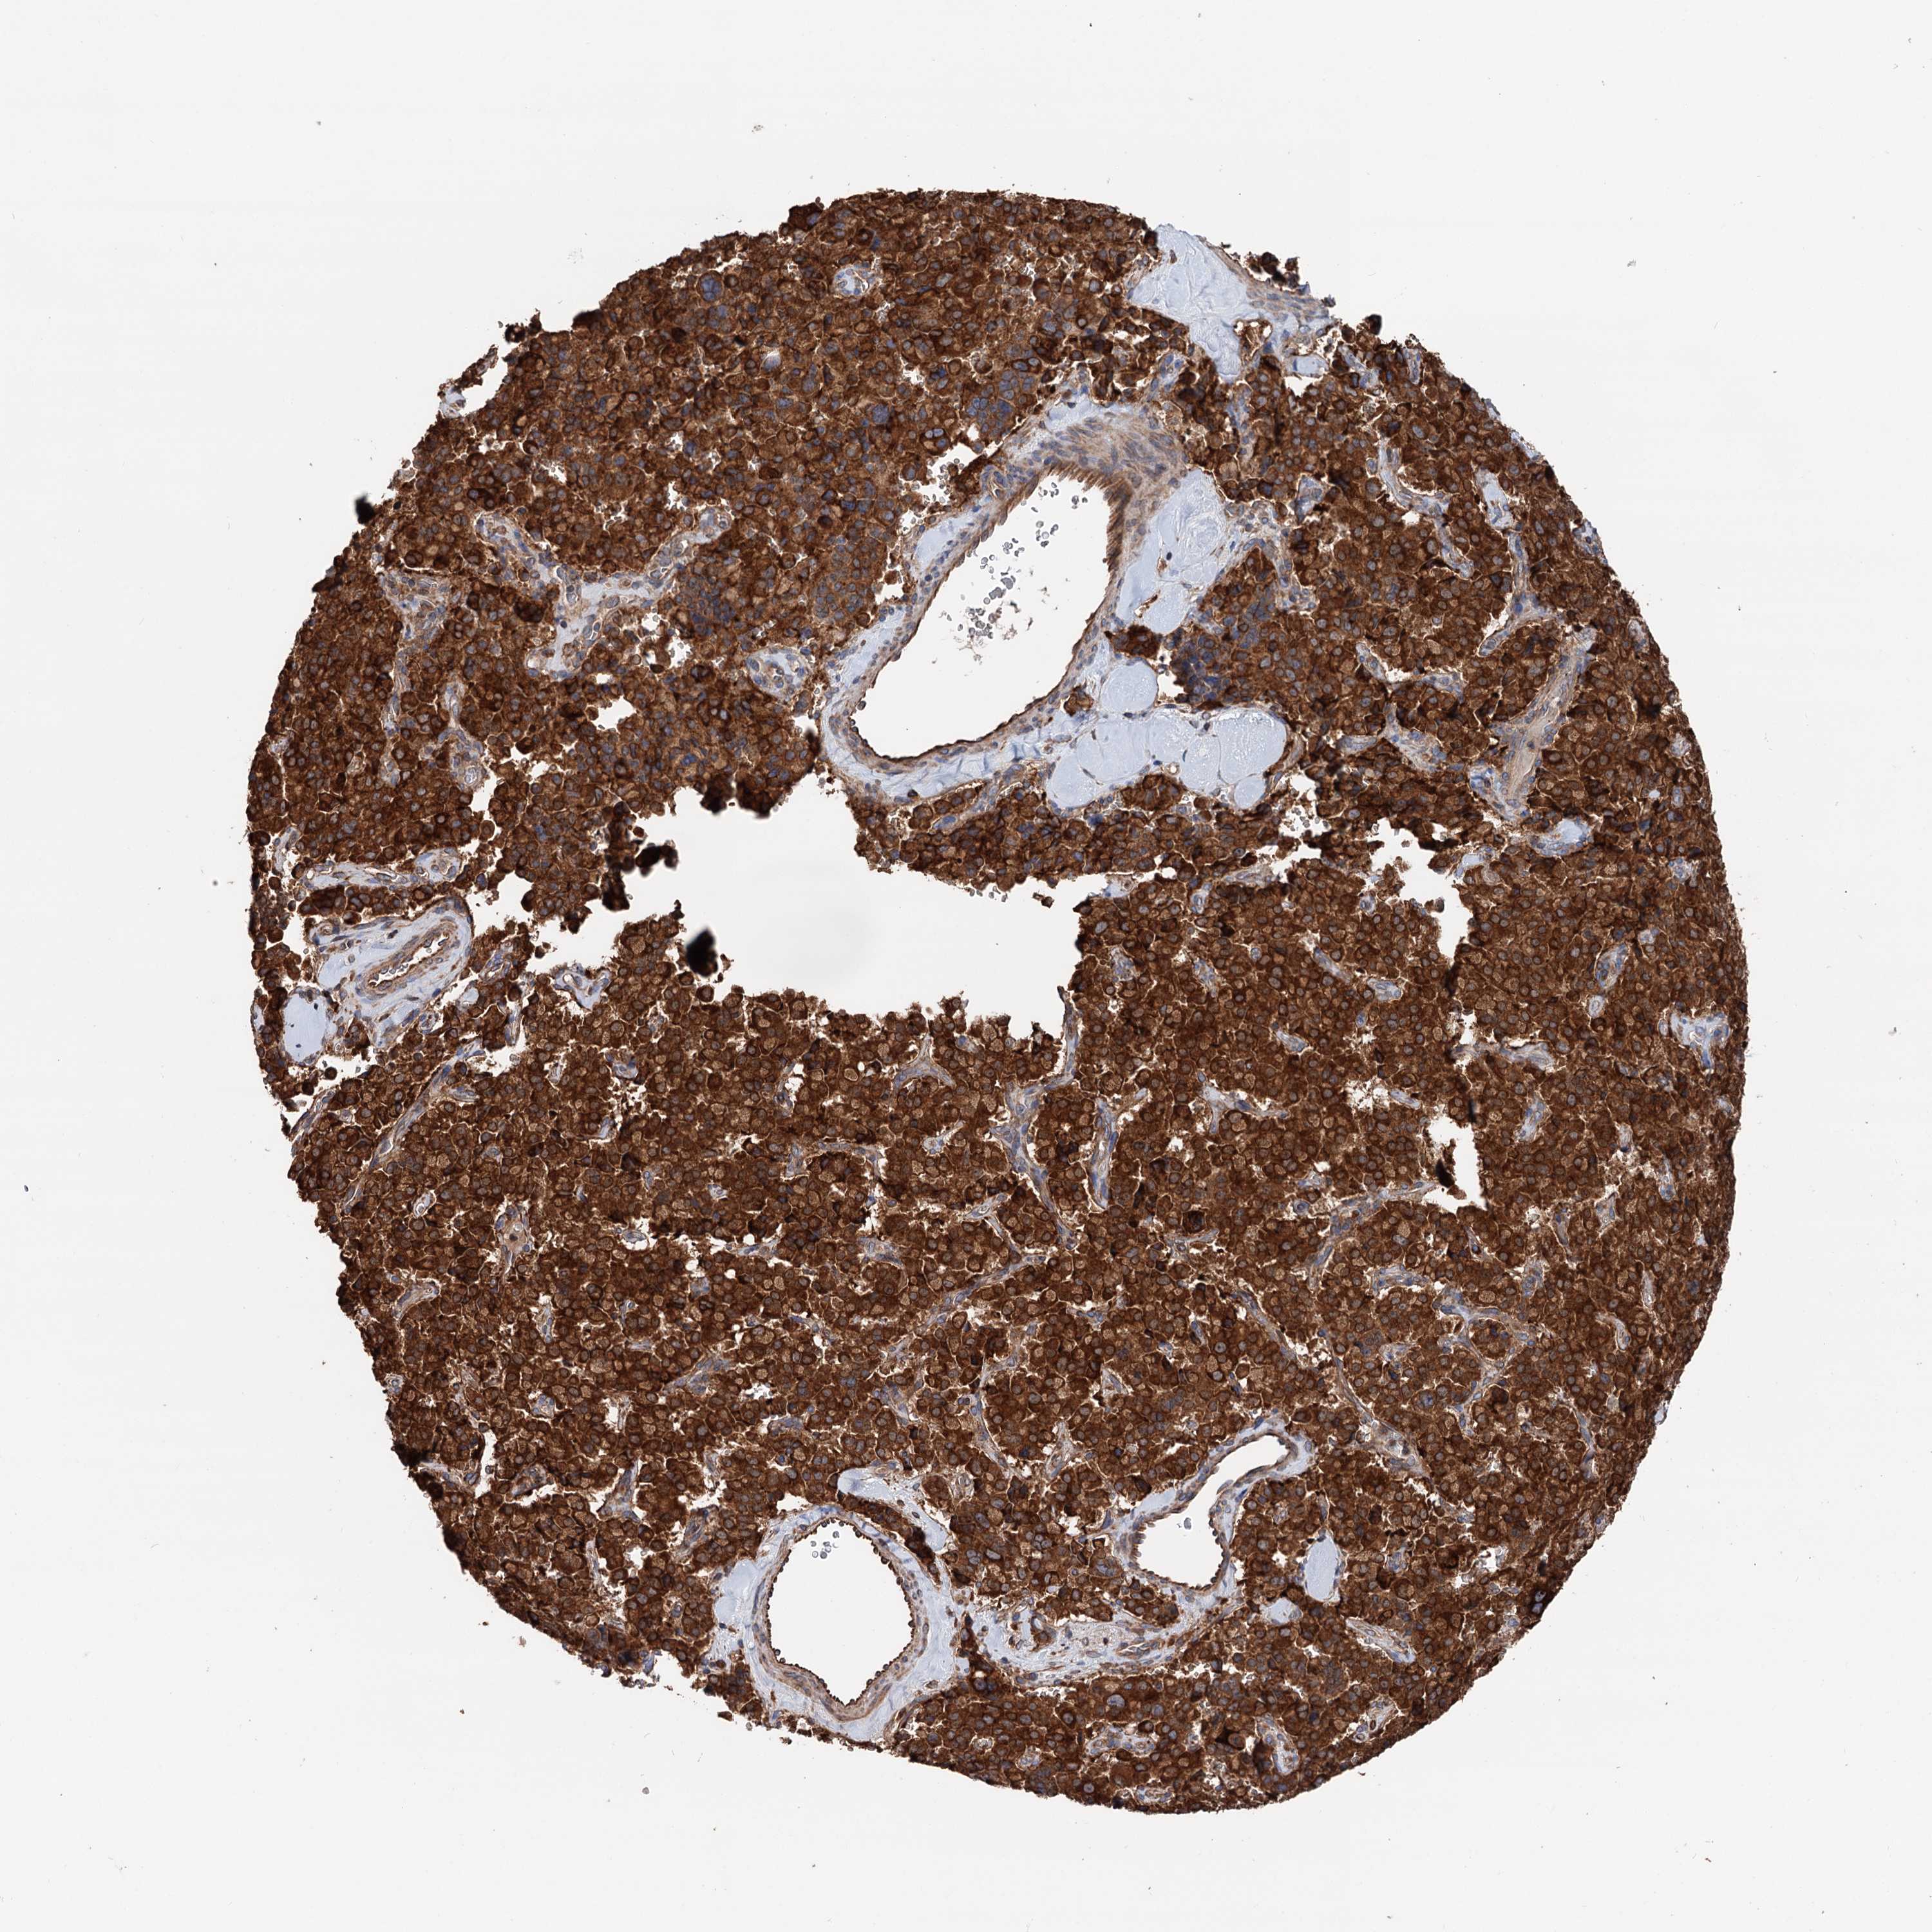

PANCREATIC CANCER - Protein expressioni

A mouse-over function shows sample information and annotation data. Click on an image to view it in a full screen mode. Samples can be filtered based on level of antibody staining by selecting one or several of the following categories: high, medium, low and not detected. The assay and annotation is described here.

Note that samples used for immunohistochemistry by the Human Protein Atlas do not correspond to samples in the TCGA dataset.

Antibody stainingi

Antibody staining in the annotated cell types in the current human tissue is reported as not detected, low, medium, or high, based on conventional immunohistochemistry profiling in selected tissues. This score is based on the combination of the staining intensity and fraction of stained cells.

Each image is clickable and will lead to virtual microscopy that enables deeper exploration of all samples and also displays staining intensity scores, fraction scores and subcellular localization as well as patient and tissue information for each sample.

Antibody HPA039363

Antibody HPA039456

Staining

High

Medium

Low

Not detected

Intensity

Strong

Moderate

Weak

Negative

Quantity

>75%

75%-25%

<25%

None

Location

Nuclear

Cytoplasmic/membranous

Cytoplasmic/membranous,nuclear

Adenocarcinoma, NOS